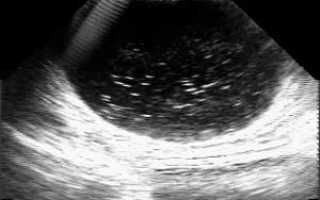

Для того чтобы обнаружить осадок в мочевом пузыре и определить его количество, проводят ультразвуковое исследование. Анализ мочи и крови необходим для определения состава конкрементов. Остальные способы медицинского обследования позволяют выявить дополнительные сведения для определения клинической картины недуга и способов его излечения.

Следует помнить, что признаки наличия в мочевом пузыре осадков появляются только со временем, на ранних стадиях патология протекает бессимптомно. Расплывчатость симптоматики влияет на правильность результата диагностики. При ощущении дискомфорта внизу живота и при процессе мочеиспускания обязательно надо пройти ультразвуковое обследование. На УЗИ взвесь в мочевом пузыре обнаружить довольно просто. Данный метод позволит выявить причину боли. Небольшой уровень взвеси уже создает изменения в толщине стенок, что свидетельствует о наличии заболевания.

УЗИ — эффективный метод проверки мочевого пузыря.

Обнаруживает УЗИ не только имеющийся осадок, но и число взвеси или камней, в момент, если конкременты стали формироваться. Ультразвуковое исследование рекомендовано для диагностических целей, потому что оно способно распознать сопрягающие заболевания, негативно действующие на общее состояние человека. УЗИ также может определить причины, спровоцировавшие осадок.

Образование гиперэхогенной взвеси, выявленной на УЗИ, свидетельствует о существовании непросто маленькой частички осадка, а, о значительном размере, камне.

Для того чтобы оценить насколько мутные околоплодные воды при беременности, то есть поставить точный диагноз, можно использовать разные методики. Одной из самых безопасных является ультразвуковое исследование. Также возможно проведение амниоскопии, когда специальный прибор вводится через шейку матки и оценивает состояние вод, не повреждая пузырь. Это обследование нередко назначают для диагностики кислородной недостаточности у плода вследствие переношенной беременности. Существует еще и метод амниоцентеза – прокола пузыря обычно через брюшную стенку матери. Эта методика также позволяет определить хромосомный набор плода. Амниоцентез обычно назначается во втором триместре беременности при подозрении на генетические заболевания у ребенка.